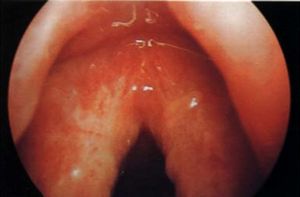

该疗法的基本原理是低温消融,即利用低温等离子射频的能量,产生强烈的分子运动,形成特殊的内生热效应,用较低温度(40~70℃)使组织蛋白液化消融,使病变组织萎缩,平复,消失或坏死脱落,新鲜粘膜再生修复,恢复咽后壁粘膜光滑,红润,平整,达到根除病变,消减症状,治愈疾病。仅需10分钟,术中无痛苦,不出血,术后无并发症,恢复快,不住院,深受广大患者的欢迎。而且非常适合于儿童的咽生殖器畸形治疗。